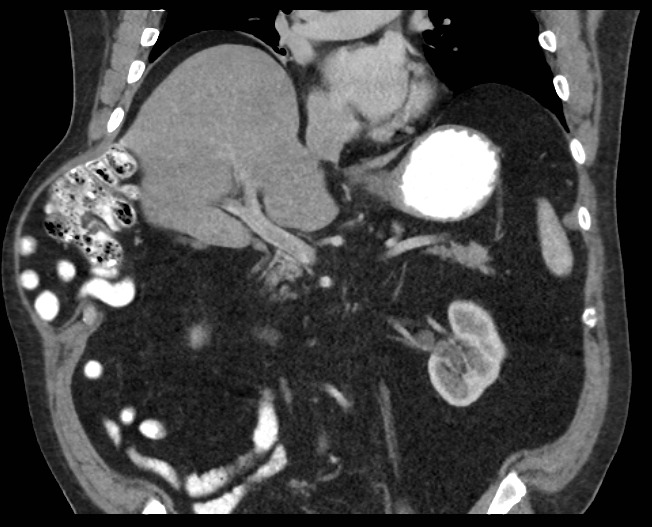

Patient #2 presented with a written report from an out of state chest CT stating the presence of an AIH. A repeat abdominopelvic CT that was performed for surgical planning revealed a similar defect to patient #1 in the right anterolateral chest wall. The hernia contents included portions of small bowel and a portion of the right colon (Figure 2).